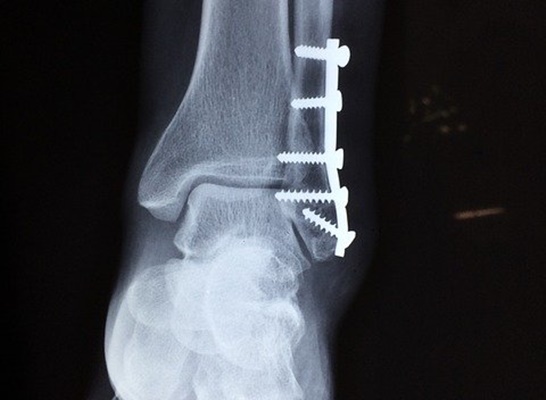

다양한 발목 관절염 증상이 나타나면 초기에 물리치료나 주사 치료, 약 처방 등을 통해서 치료를 진행하게 됩니다. 하지만 증상이 심하고 초기 치료에 실패하게 되면 중장기 관절염으로 판단하고 수술적 요법을 사용하여 치료해야 합니다. 중증 발목 관절염 치료는 인공 관절을 대체하는 수술로 조치 되기도 합니다.